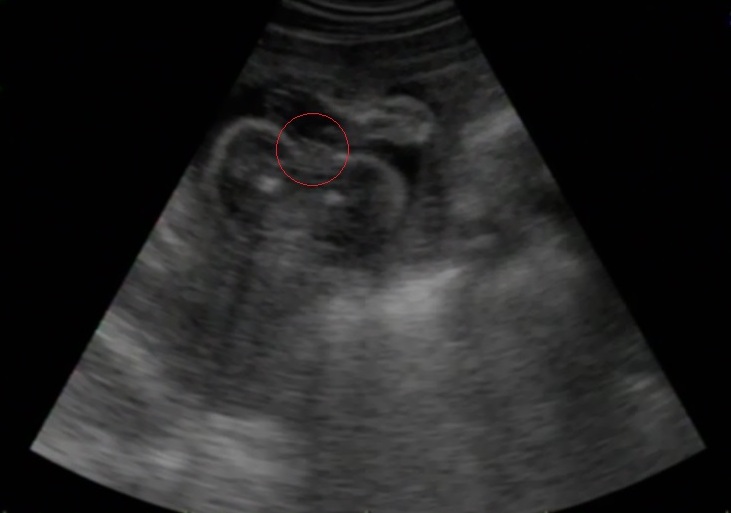

je to holka nebo kluk ?

já to tam vidím vcelku jasně, ale manžel vidí jen "tmu, mlhu a sněhovou vánici"

doktor neřekl nic, je to fotka střihlá doma z videa ve 23.týdnu.. pátrala jsem a pátrala a.................??? podle mě jasná holka!!

čekala jsem na další utz a tohle je teda výsledek no.....